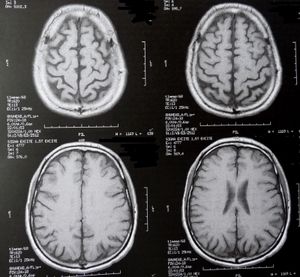

Gehirn-Scans: Forscher untersuchen Eiweiße (Foto: pixelio.de, Dieter Schütz) |